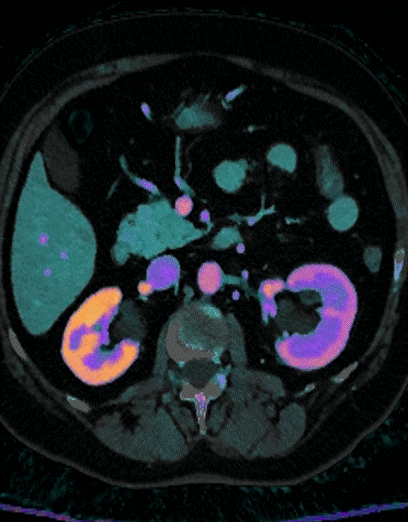

Spectral CT, iodine overlay: Note delayed nephrogram in left kidney.